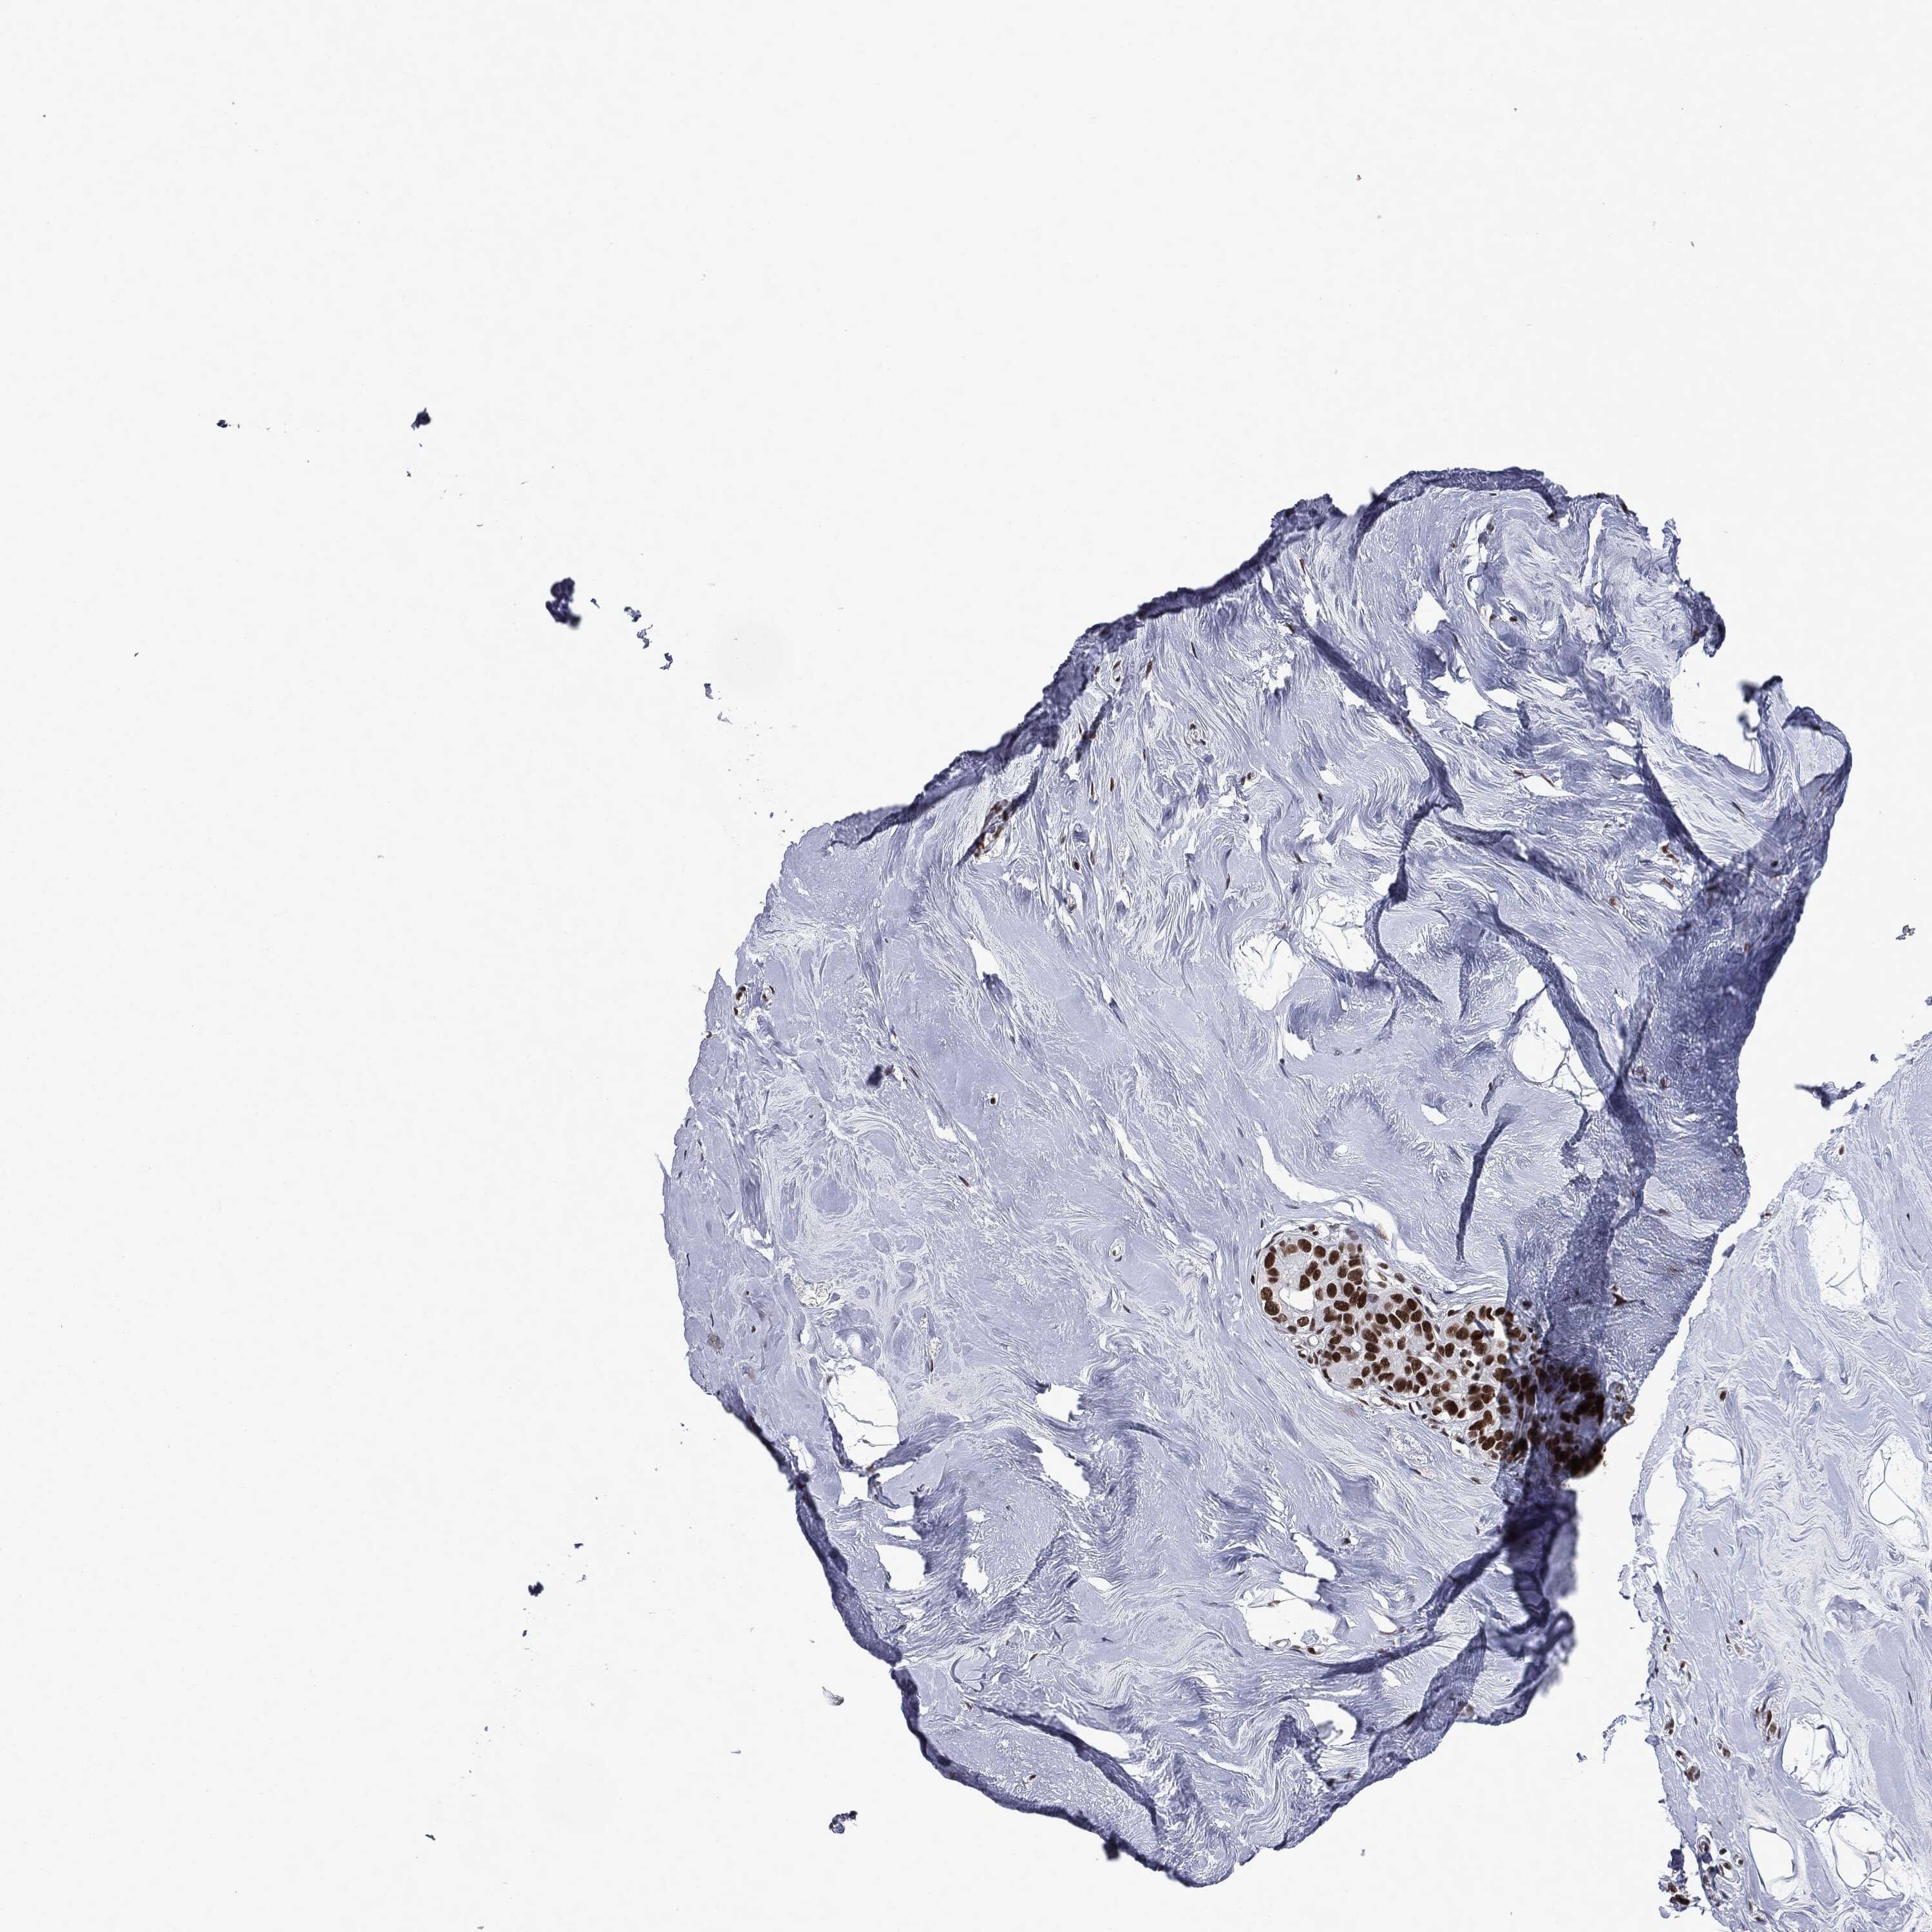

BRCA TCGA BRCA VALIDATION PROTEIN EXPRESSION